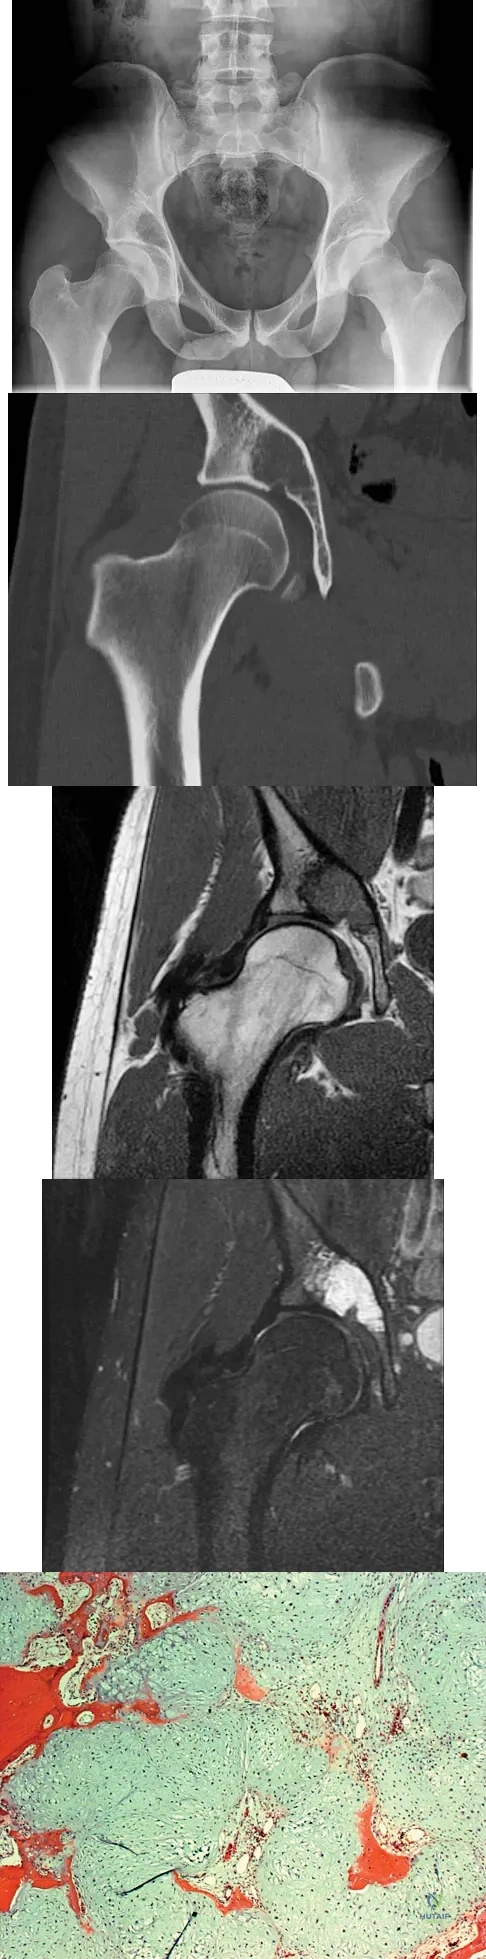

A 21-year-old man has had right groin pain for the past year. A radiograph, CT scan, MRI scans, and a biopsy specimen are shown in Figures 50a through 50e. What is the most likely diagnosis?

Explanation